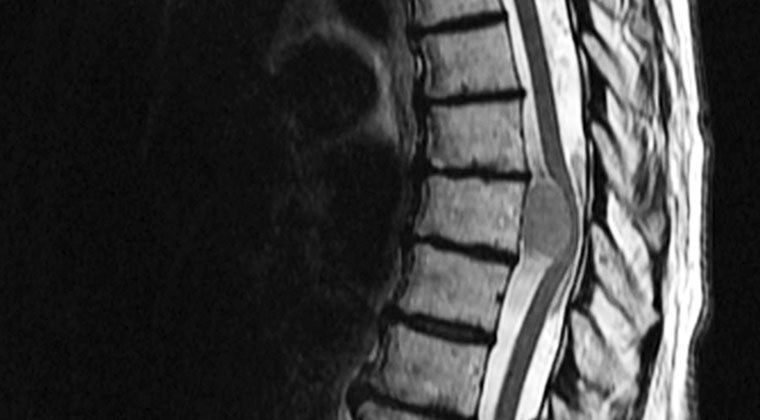

Benign back pain is a very common occurrence. However, presence of few signs and symptoms can indicate more sinister cause of back pain. These red flags are: - age more than 50 or less than 20 - history of trauma - history of malignancy - severe or progressive altered sensation - severe or progressive motor weakness - urinary and fecal incontinence or retention - use of immunosuppression drugs - intravenous drug abuse - numbness in perineal region - unexplained weight loss - constitutional symptoms Reference: Bailey and Love's Short Practice of Surgery Image via: https://www.christopherreeve.org/living-with-paralysis/health/causes-of-paralysis/spinal-tumors